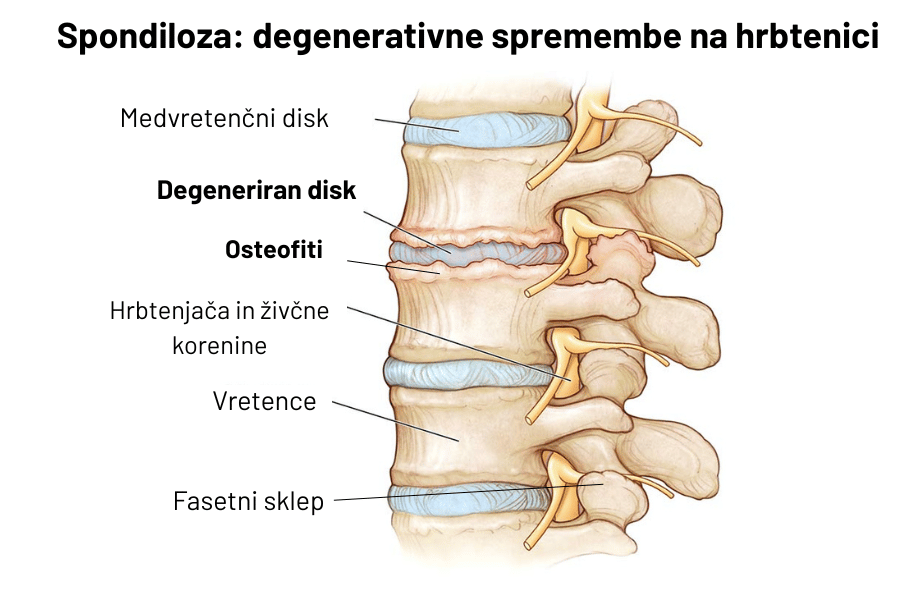

Spondiloza se pogosto prične z degeneracijo medvretenčnih diskov, kjer zaradi določenih sprememb, ki se dogajajo tekom staranja (npr. zmanjšan delež vode in proteoglikanov – sestavine diskov, ki je odgovorna za njihove mehanske lastnosti), pride do strukturnih in funkcionalnih sprememb v diskih. Diski postanejo »izsušeni«, manj elastični in manj odporni na stres oz. mehanske sile, zmanjšata se tudi njihov volumen in višina.

Posledica teh sprememb je zmanjšana sposobnost absorpcije sil, zato se mehanski stres, ki ga diski ne uspejo absorbirati, prenese na okolne strukture: vretenca, fasetni sklepi (sklepi, ki so med vretenčnimi izrastki). Zaradi povečanja lokalnih mehanskih sil na vretenca se lahko začnejo tvoriti tudi osteofiti oz. kostni izrastki. Včasih pa so diski relativno dobro ohranjeni in se degenerativne spremembe pričnejo v fasetnih sklepih (ali pa kot tvorba osteofitov med vretenci), kar je običajno posledica ponavljajočih mehanskih obremenitev na hrbtenico, o čemer bo govora v nadaljevanju zapisa.

Sledi srednja oz. reaktivna faza, pri kateri se zaradi znižanih (posedenih) diskov obremenitve prenašajo na okolne strukture: na fasetne sklepe in ligamente. Deli hrbtenice imajo lahko zmanjšano gibljivost. V tej fazi je prisotnih največ simptomov: bolečina, okorelost in zmanjšana odpornost na vsakodnevne obremenitve. Kot posledica obremenitev na strukture se lahko začnejo tvoriti osteofiti oz. kostni izrastki.

Tvorba osteofitov je pravzaprav prilagoditev telesa na povečane sile na vretenca, ki jih diski ne uspejo več učinkovito amortizirati. S tvorbo novega kostnega tkiva na robovih vretenc telo poskuša zagotoviti manjkajočo stabilnost in zmanjšati stres na vretenca. Zaradi novega kostnega tkiva se nekoliko poveča površina vretenca, kar pomaga pri razporeditvi mehanskih sil na širše področje. Sama tvorba osteofitov načeloma ni problematična, razen če novonastalo tkivo posega v področje živcev in/ali ožilja in če znatno omejuje gibljivost vretenc.